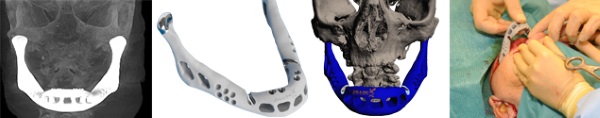

在2012年的時候,比利時和荷蘭的科學(xué)家為一個83歲女士成功的更換了一副用鈦金屬3D打印的下頜,這副下頜就是由LayerWise負(fù)責(zé)制造的。當(dāng)時是6月份在 Sittard-Geleen的醫(yī)院進(jìn)行的手術(shù),一天后這位女士就已經(jīng)可以開始說話、吞咽了。LayerWise也因此名聲大振。